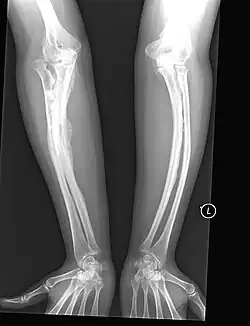

The most direct example of the role of Sp7 in human disease has been in recessive osteogenesis imperfecta (OI), which is a type-I collagen related disease that causes a heterogeneous set of bone-related symptoms which can range from mild to very severe. Generally this disease is caused by mutations in Col1a1 or Col1a2 which are regulators of collagen growth. OI-causing mutations in these collagen genes are generally heritable in an autosomal-dominant fashion. However, there has been a recent case of a patient with recessive OI with a documented frameshift mutation in Sp7/Osx as the etiological origin of the disease.[11] This patient displayed abnormal fracturing of the bones after relatively minor injuries and markedly delayed motor milestones, requiring assistance to stand at age 6 and was unable to walk at age 8 due to pronounced bowing of the arms and legs. This provides a direct link between the Sp7 gene and the OI disease phenotype.